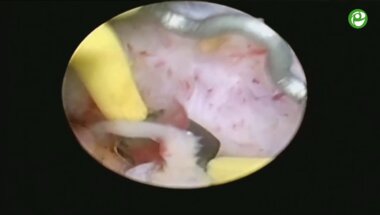

Биполярная электроэнуклеация гиперплазии простаты